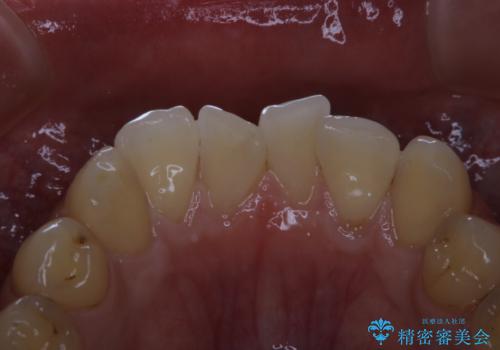

細かいステインをPMTCでOFF

- 歯ブラシをしてもとれないステインが気になるとのことで来院されました。PMTC60分コースを行いました。

PMTCは、歯に付着した汚れを除去していくため、着色が気になる場合にも行うことができます。ご自身でのセルフケアだけで着色を落とそうとすると、逆に歯を傷つけてしまったり、精密に汚れを除去できないこともあります。また、日常生活で着色しやすい飲食物を避けたりすることはストレスに感じてしまったり、あまり現実的ではありません。

毎日丁寧に歯磨きをしていても、日常生活での飲食物などにより着色してしまうことはあります。PMTCでは、歯の表面の凸凹にミネラルを補給して、ツルツルの表面に仕上げます